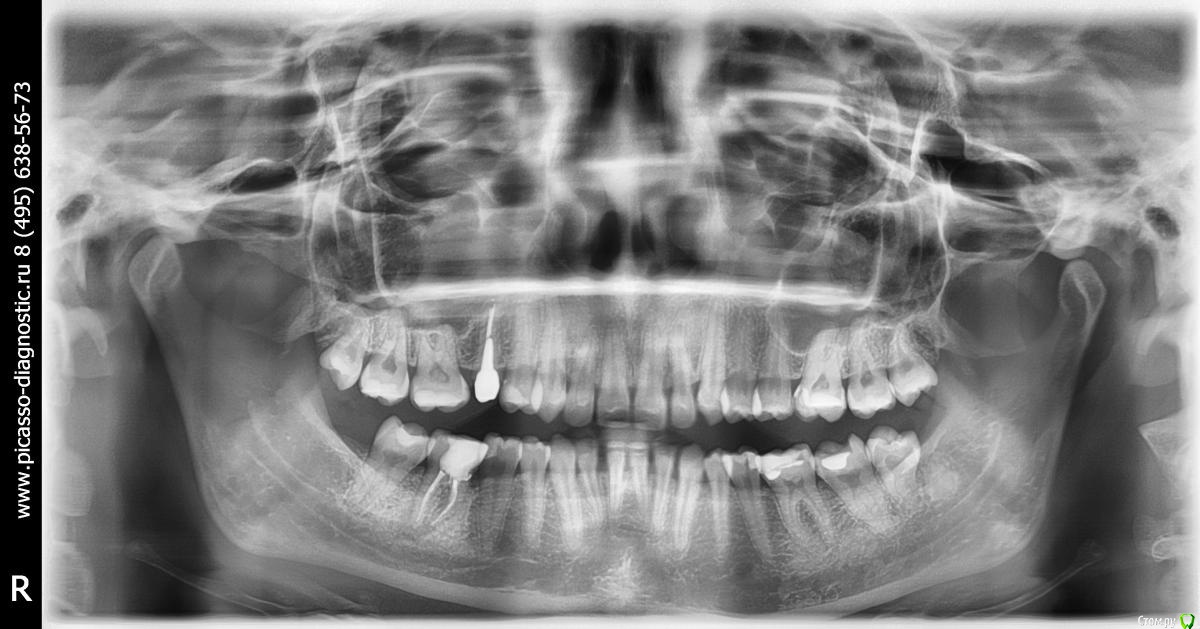

P.S. Было бы неплохо если бы Вы сделали ОПТГ в прикусе и выложили бы снимок.

ОТПГ снимок приложила в первом посте, он есть среди прочих! Если Вы не что-то другое имели в виду. :huh:

Необходимо сделать ОПТГ в прикусе (при всех сомкнутых зубах) или кт височно-нижнечелюстного сустава. Тогда будет понимание о смещении/положении самой нижней челюсти.

По Трг Вам однозначно необходимо удаление зубов на в.ч, а возможно и на н.ч т.к очень сильный наклон передних зубов.